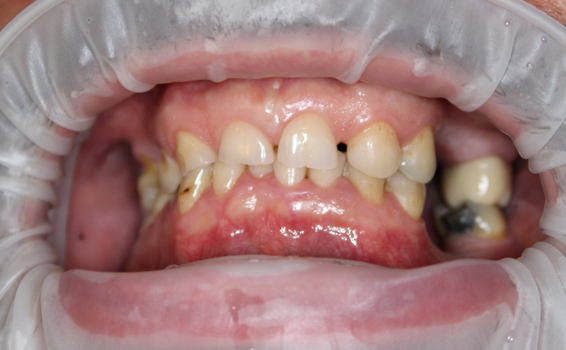

Avant

photo-avant-soins-dentaires

Situation dentaire avant soins : plusieurs dents manquantes et des dents affaiblies.

Souhait de Michel : retrouver une dentition complète et esthétique.

Soins réalisés : réhabilitation complète des deux arcades

• Maxillaire supérieur : allongement coronaire, pose de 4 implants, puis 12 couronnes et bridges céramiques zircone.

• Maxillaire inférieur : extractions, pose de 3 implants, puis 12 couronnes et bridges céramiques zircone.